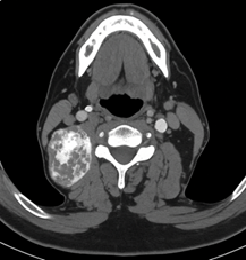

At the level of the left trachea, the thyroid gland appears heterogeneous and enlarged due to the presence of a heterogeneous and irregular mass with contrast enhancement extending into the mediastinum, loss of the interface with the trachea, and inadequate interface with the esophagus. The mass measures 81 x 49 x 42 mm (Figure 2).

Computed tomography of the neck. The thyroid gland appears heterogeneous and enlarged, with an irregular mass demonstrating contrast enhancement that extends into the mediastinum.